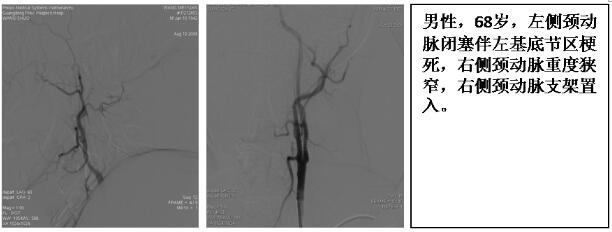

2.脑血管病及脑血管介入:在国内较早建立了卒中单元和脑血管介入诊疗组,建立多学科合作的卒中绿色通道, 24全天候急诊脑血管介入值班,开展了全脑血管造影术(DSA)、静脉溶栓、动脉溶栓术及动静脉联合溶栓术、大血管急性闭塞取栓及支架置入、颅内、外脑供血动脉狭窄球囊成形术、支架植入术、复杂高危脑动脉狭窄的血管内介入治疗术、颅内外脑动脉慢性闭塞的再通治疗等;诊治水平处于国家先进行列,年导管量约1500例次。